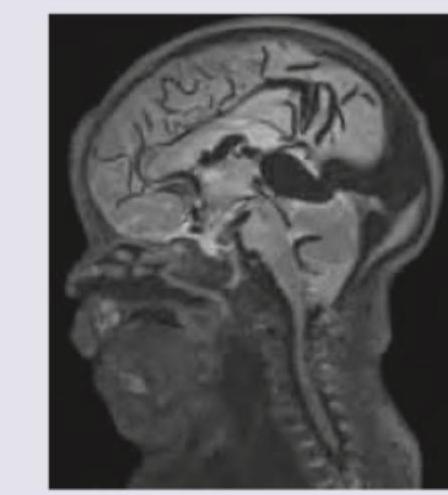

A 6 month infant was brought with complaints of a failure to gain weight and a large head. On examination, increased head circumference, bounding pulses and features of heart failure were noted. On cranial auscultation loud cranial bruit was heard. MRI head shows? (Recent NEET Pattern 2018-19)

Explanation: ***Vein of Galen formation*** - The clinical presentation of **failure to thrive**, **macrocephaly**, **bounding pulses**, **heart failure**, and a **loud cranial bruit** in an infant is highly characteristic of a **Vein of Galen malformation (VOGM)**. The image would show a dilated vein of Galen. - VOGMs are high-flow arteriovenous malformations that can lead to significant hemodynamic stress on the heart and hydrocephalus due to obstruction of CSF pathways. *Arachnoid cyst* - While arachnoid cysts can cause **macrocephaly** and, less commonly, obstructive hydrocephalus, they generally do not present with **heart failure**, **bounding pulses**, or a **cranial bruit**. - MRI would show a CSF-filled cyst that follows CSF signal on all sequences and typically does not enhance. *Arnold-Chiari malformation* - Arnold-Chiari malformations involve downward displacement of cerebellar tonsils or vermis through the foramen magnum and are associated with hydrocephalus, but they do not typically cause **heart failure**, **bounding pulses**, or a **cranial bruit**. - Clinical features usually relate to brain stem compression or hydrocephalus, such as apnea, stridor, or feeding difficulties. *Dandy-Walker syndrome* - Dandy-Walker syndrome is characterized by hypoplasia of the cerebellar vermis and cystic dilation of the fourth ventricle, often leading to **hydrocephalus** and **macrocephaly**. - However, it does not explain the **bounding pulses**, **heart failure**, or **cranial bruit** seen in this patient, which point to a vascular anomaly.